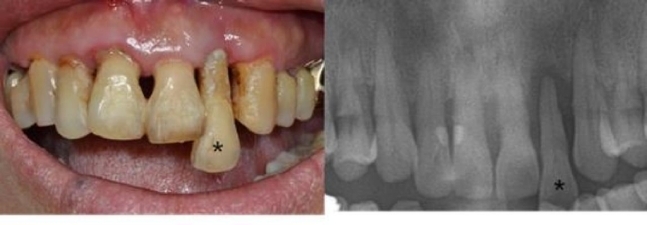

치주질환은 입안에 남아있는 음식물 찌꺼기와 세균이 만나 생긴 플라그로 인해 잇몸과 치아가 점차 멀어지면서 그 공간이 커져 잇몸이 가라앉거나 피가 나는 질환이다.

서울대학교치과병원은 구강 내 세균과 음식물에 의해 형성되는 치태는 제때 제거하지 않으면 치석을 만들어 치주질환을 유발한다며 치석이 잇몸과 치아 사이를 벌어지게 하고 이 사이에 세균이 침투해 염증이 심해진다. 잇몸이 붓거나 피가 나는 증상을 동반한다고 설명했다.